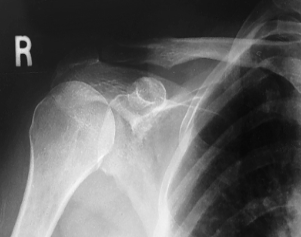

is this a normal or dislocated shoulder? how do you know?

normal, head of humerus superimposed over base of Y